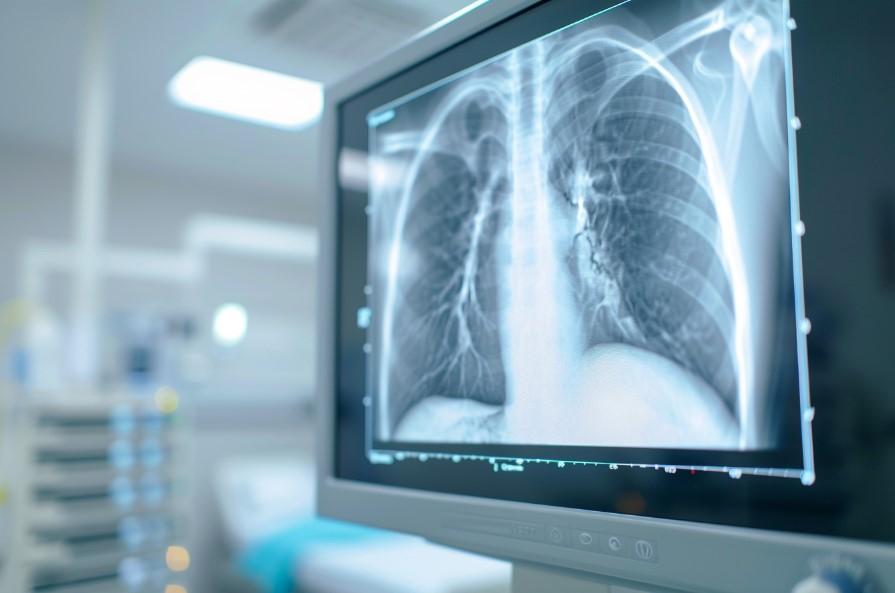

Информацию из данного раздела нельзя использовать для самодиагностики и самолечения. В случае боли или иного обострения заболевания диагностические исследования должен назначать только лечащий врач. Для постановки диагноза и правильного назначения лечения следует обратиться к профильному специалисту.